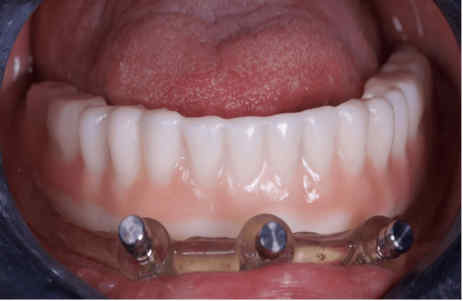

The provisional prosthesis was directly relined and secured using titanium abutments and flowable resin (Figures 9, 10). The installation of the temporary prosthesis for immediate loading was performed (Figure 11). The final panoramic radiograph and tomography image showing the result was obtained, revealing the implant placement with immediate provisional fixed rehabilitation (Figures 12, 13).

FIGURE 11: Installation of the temporary prosthesis for immediate loading

FIGURE 13: Final occlusion – frontal view